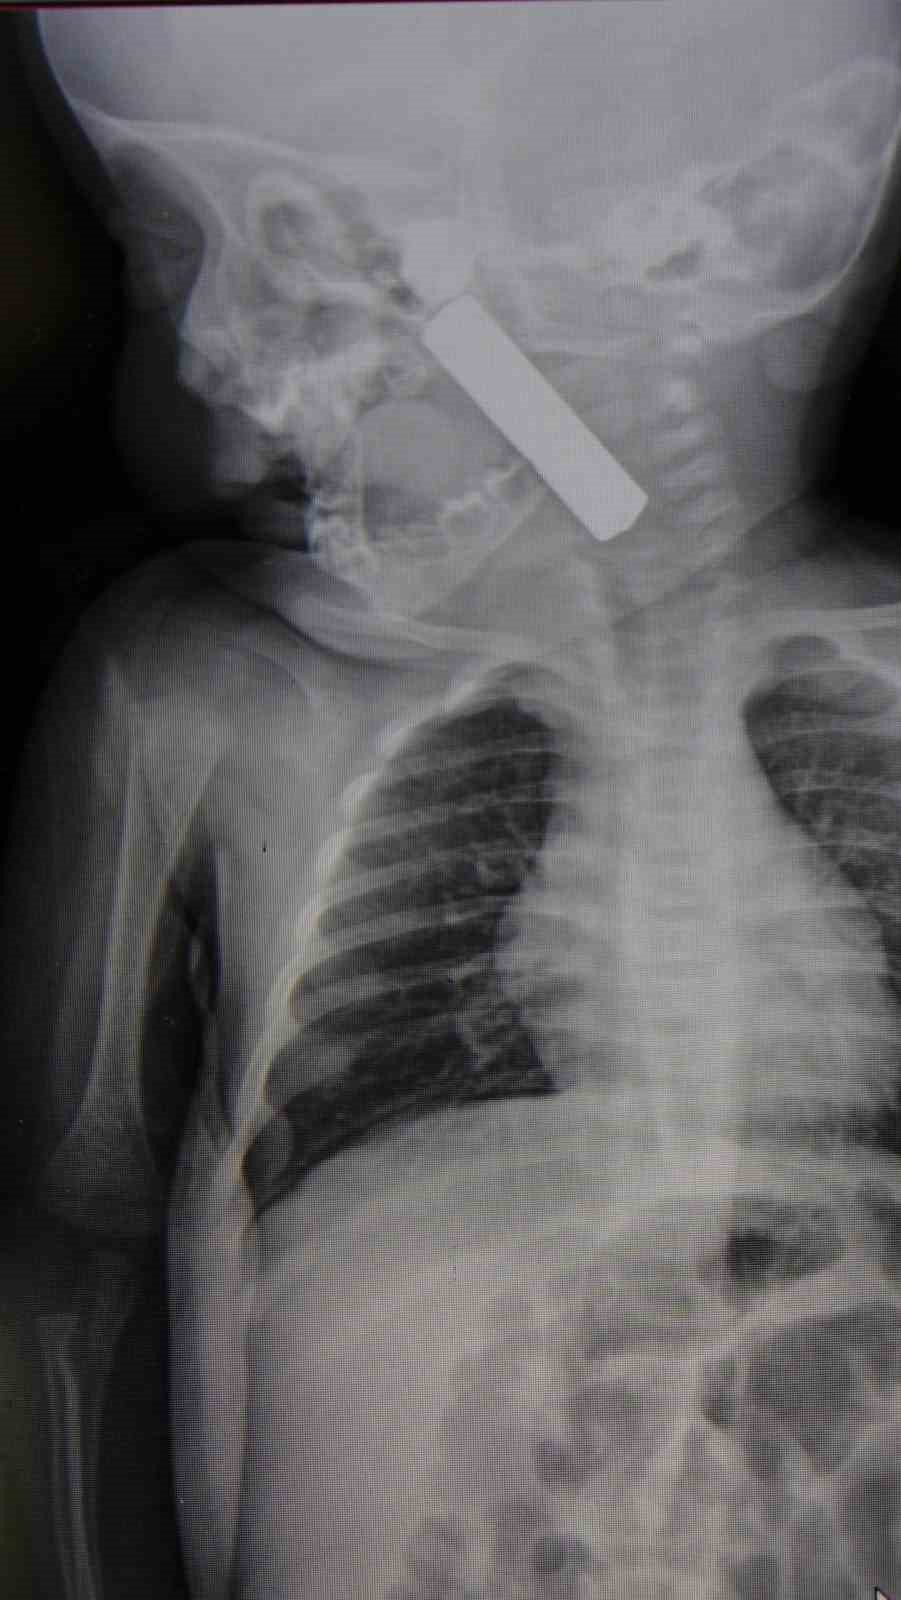

Karaman’da 6 aylık E.A. isimli kız bebek, kusma şikâyetiyle ailesi tarafından Karaman Eğitim ve Araştırma Hastanesi acil servisine getirildi. Yapılan muayene ve tetkiklerde, bebeğin boğazına kumanda pili kaçtığı tespit edildi.

Solunum sıkıntısı yaşadığı belirlenen bebek, zaman kaybedilmeden ameliyata alındı. Çocuk Cerrahisi Uzmanı Doç. Dr. Mehmet Uysal tarafından gerçekleştirilen müdahaleyle, bebeğin boğazındaki pil başarılı şekilde çıkarıldı.

Operasyonla ilgili bilgi veren Doç. Dr. Mehmet Uysal, bebeğin acil servise getirildiğinde durumunun kritik olduğunu belirtti. Yapılan incelemelerde, yabancı cismin ağız tabanına oturduğu ve yemek borusunun ilk darlığına kadar uzandığının görüldüğünü ifade etti.

Uysal, bebeğin ilk muayenede siyanotik durumda olduğunu, oksijen satürasyonunun 90 civarında seyrettiğini belirterek, hızlı şekilde ameliyathaneye alındığını kaydetti. Yapılan işlemle yabancı cismin çıkarıldığını ve oluşan hasar nedeniyle bebeğin 24 saat gözlem altında tutulduğunu aktardı.